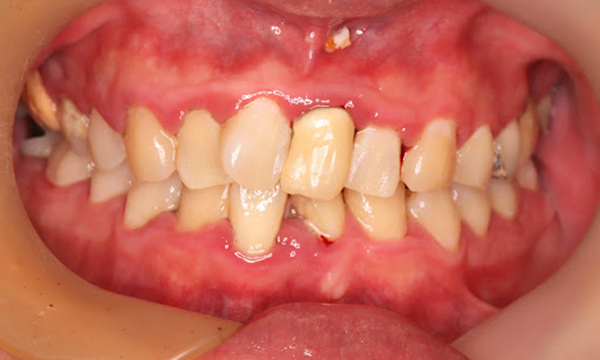

症例5

before

症例

after

歯周病検査(治療前)

歯周病検査(治療後)

レントゲン写真

基本情報

年齢・性別 32歳・男性

主訴 主訴:歯ぐきから出血する

治療部位:全顎

治療内容 「全顎」

歯周基本治療(歯周精密検査、スケーリング、OHI、SRP)

治療期間 約3ヶ月

治療費 歯周基本検査:約600円(保険診療3割負担)

スケーリング、OHI:約2,000円(保険診療3割負担)×2回

SRP、OHI:約1,500円(保険診療3割負担)×4回

歯周精密検査:約1,200円(保険診療3割負担)×2回

合計金額13,000円

(2025年2月現在)

リスク・副作用 歯石を取った後に、歯がしみることがあります。

治療方針 ①検査

レントゲン、口腔内写真を撮影して、歯や歯周組織の状態を確認します。

また、歯周病の検査で歯周ポケットの深さや出血の有無を確認します。

②スケーリング、OHI(口腔衛生指導)

スケーリングをして歯の表面の歯石を除去します。

また、正しい歯磨きの仕方や、フロスの通し方を一緒に確認します。

③歯周精密検査

前回歯石除去と歯磨き指導を行なった結果、歯ぐきの状態がどれぐらい改善したか検査します。

④SRP

歯ぐきの内側についてる歯石を除去します。

⑤歯周精密検査

SRP後、歯周病が改善されたか、検査します。

歯周ポケットが4ミリ以上の部位は、再度SRPを行います。

今回は歯周病の状態が安定したため、3ヶ月おきの定期検診で歯周病の再発や進行を防ぎます。

特記事項 歯周精密検査について:

・歯周ポケットが4ミリ以上ある場合は歯周病で、3ミリ以下は健康な歯ぐきです。

・出血の有無で炎症があるか確認します。

・磨き残しがある部分を確認して記録します。

担当者所見 初診時は、写真を見て分かるように、歯ぐきが赤く腫れていました。

また、歯周病の検査では、全体的に歯と歯の間の部分の歯周ポケットが4ミリあり、全体の約81%から出血が認められました。

出血量も多く、歯ぐきに触れた瞬間に出血しました。

レントゲンで骨のレベルがしっかりとあることが確認できました。

そのため、ご自身で正しい歯磨きを継続することで改善すると考えました。

歯周基本治療を経て、再度検査した結果、歯周ポケットはほぼ3ミリ以下に改善しました。左下7番の残存した歯周ポケットは、隣の親知らずを抜いたため経過観察します。

出血率は約4%まで改善し、出血量も点状で少なくなりました。

今後は右上2番、右下3番の歯ぐきの発赤の改善と、出血率0%を目指して、定期検診でメンテナンスしていきます。